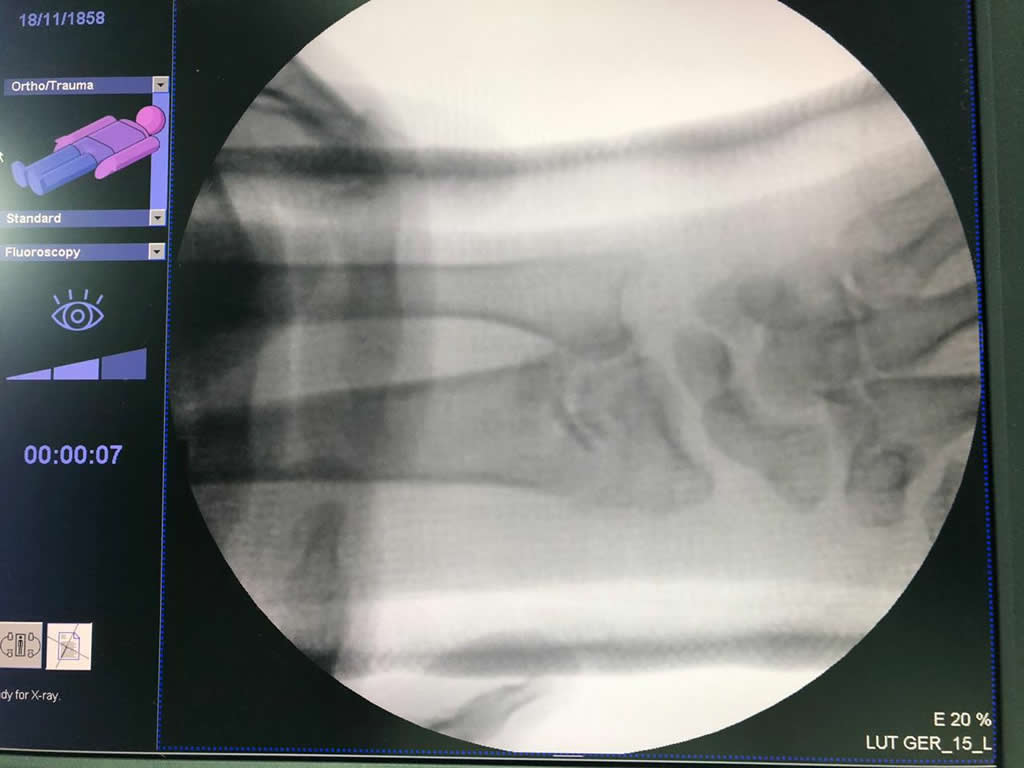

Cirugías de Codo - Cirugías de Muñecas y Manos

Los procedimientos más comunes en cirugía de la mano son aquellos destinados a reparar traumatismos, incluyendo lesiones de tendones, nervios, vasos sanguíneos, y articulaciones; huesos fracturados; y quemaduras, cortes, y otros daños de la piel.